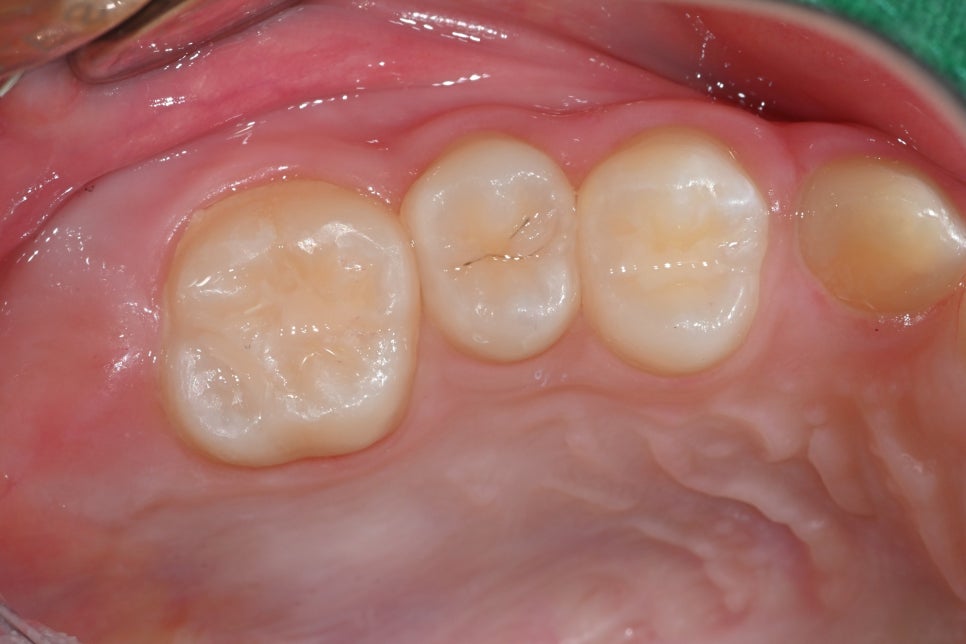

✅ 치료 후 사진 (03.18)

급여 레진 수복 후 자연스럽게 복원된 어금니 모습입니다

치료는 급여 레진 수복으로 진행되었으며, 통증 없이 일상생활이 가능하고 심미적으로도 매우 자연스럽게 회복되었습니다.